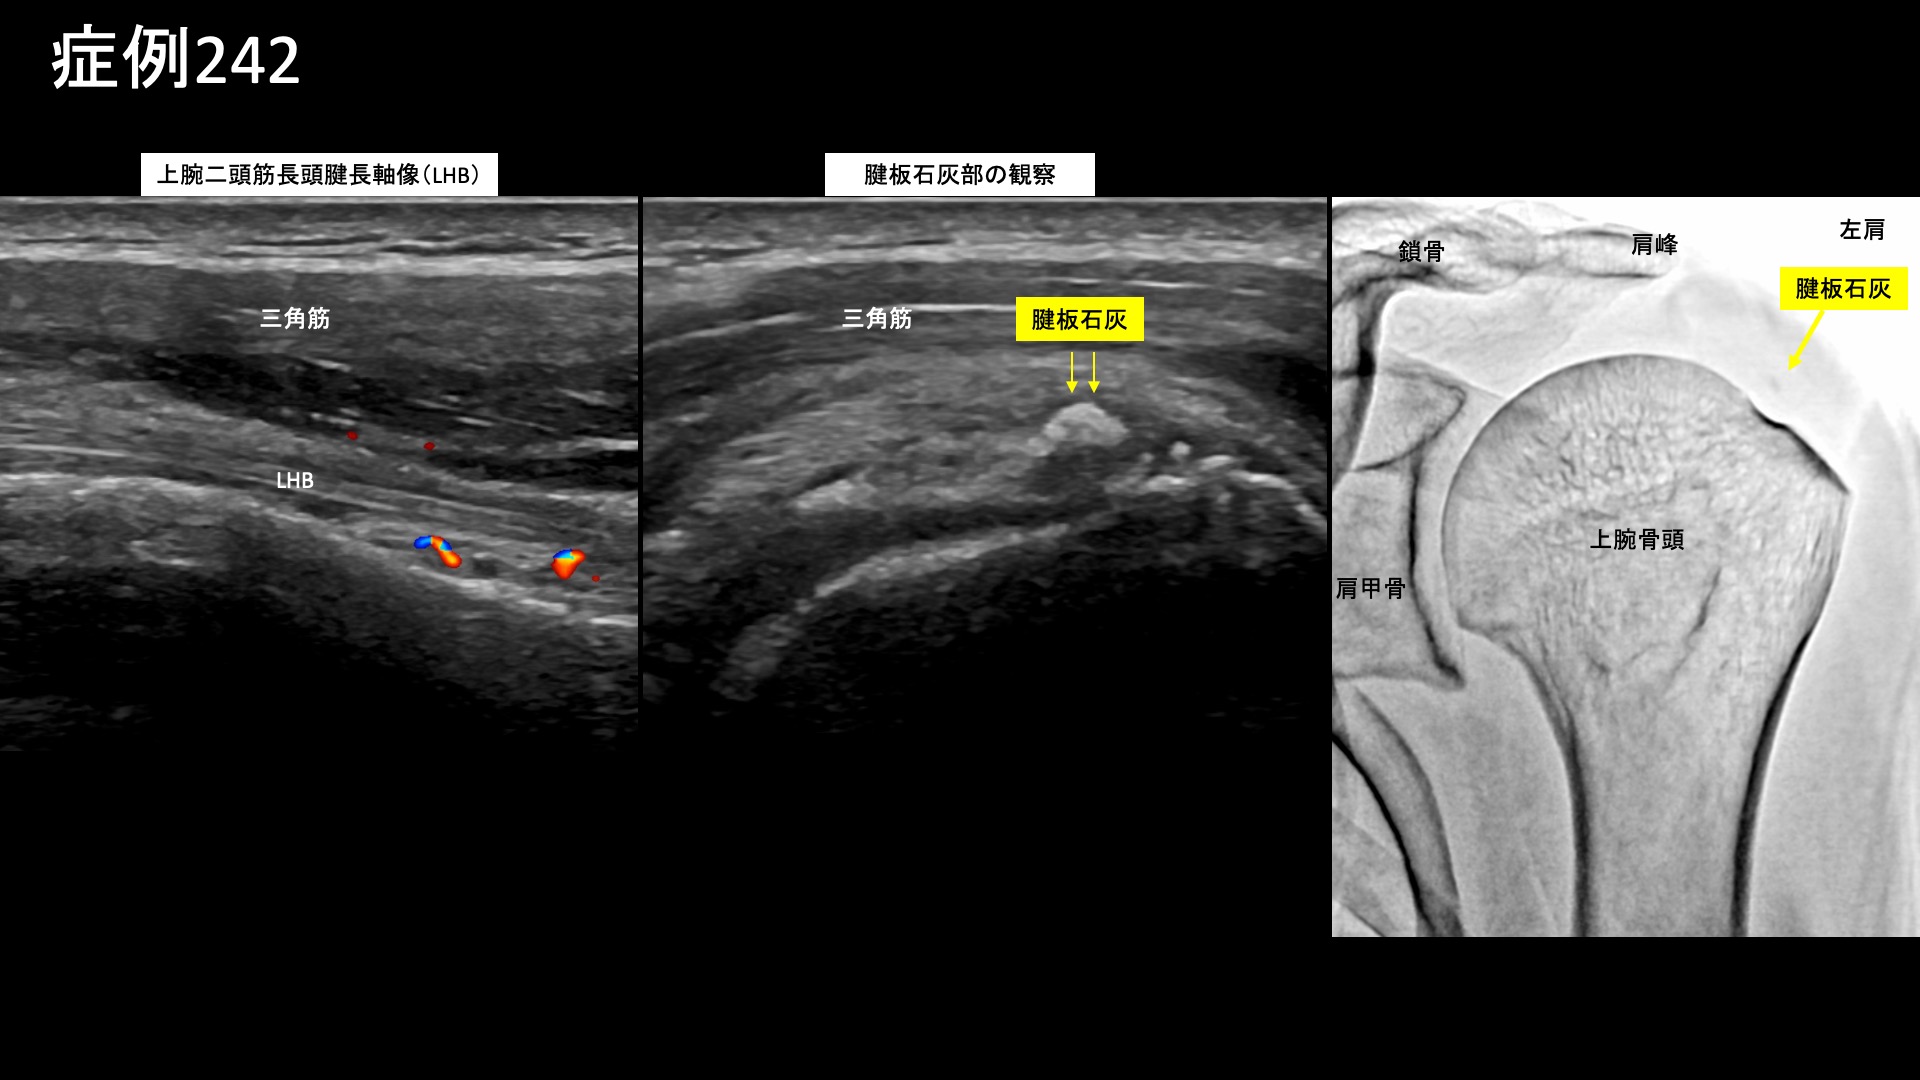

肩:肩こり・四十肩・五十肩 【50代:男性】真っすぐに座ると首から腕に激痛が・・車の運転がつらい・・重症首肩こりに対するモヤモヤ血管治療(首肩こり、頸椎症性神経根症) 2025.10.09 鴨井院長による動画解説 受診までの経過 3年前から首に違和感がありました。4ヶ月前に左肩に強烈な痛みが走り、レントゲン検査・MRI検査を受けたところ、症状の無い右肩も含めて両肩腱板に石灰沈着を認め、石灰沈着性腱板炎およびストレートネックと言われました。リハビリの方針となりましたが、効果を感じられず通院を止めていました。その後、1ヶ月前頃からは異なる症状が出てきて、背骨が真っ直ぐになるような姿勢をとると首~左肩~左腕にかけて痛むようになりました。特に椅子に座ると顕著であり、車の運転が日常的に苦痛となりました。治療方法を求めて当院を受診されました。 診察時の所見 症状の性状からは、肩関節周囲炎ではなく、頸椎症性神経根症や、重症の首肩こりである頸肩腕症候群などが疑われました。やはり、両肩関節の可動域は問題ありませんでした。一定の動作時時は見られました。首の可動域は中等度制限されており、特に後屈ではより顕著でした。レントゲンでは、頸椎は比較的保たれていました。肩関節では右側で腱板領域に粗大石灰を、左側でも少量の石灰沈着が見られました。しかしながら、エコー検査ではこれらの石灰沈着部周囲には炎症所見は見られず、陳旧性のものであることが示唆されました。一方、上腕二頭筋長頭腱周囲には水腫が見られるなど一定の炎症所見が認められました。また、棘上筋腱の部分断裂も認められました。以上より、首肩こり、および軽度の両側肩関節周囲炎(有痛性腱板損傷および、石灰沈着性腱板炎後遺症)と診断しました。治療適応と判断し、モヤモヤ血管(病的新生血管)に対する運動器カテーテル治療(微細動脈塞栓術)を受けていただきました。 治療の所見 血管造影を行うと、やはり肩関節のモヤモヤ血管よりも頸部のモヤモヤ血管の方が目立っていました。特に左頸部における深頸動脈造影においてモヤモヤ血管が濃染像として描出されました。治療後は画像上速やかに消失しました。その他複数箇所の治療を行い終了しました。 治療後の経過 治療当日から改善し、治療後2週間では、ほとんど痛みが気にならなくなりました。首を動かした際に時折つんとするような痛みが出る程度でした。よく眠れるようにもなりました。『正直半信半疑だったが、良くなってうれしい』と言われました。その後、痛みではないものの首から肩にかけてずーんと感じることはありましたが、治療後2ヶ月半になると痛み・こりともほぼ消失しました。運動習慣も取り入れていただき、様子を見ることとしました。その後も左頸部~肩の症状はぶり返すことなく順調に経過されています。尚、腱板石灰についてはやはり陳旧性のものであり、症状改善後も残存していました。新鮮なものではないため、自然吸収は期待できませんが、残存していても痛みなく過ごせる方は多いです。本症例は、頸部由来の上肢に至る神経症状をきたしている状態でした。頸椎症性脊髄症については治療効果に限界がありますが、神経根症までの段階、あるいは筋・筋膜・血行などに起因するいわゆる重症の首肩こりであれば、モヤモヤ血管に対する運動器カテーテル治療が非常に有効です。治療後は、痛みの改善だけでなく、よく眠れるようになった、眠りが深くなった、身体が軽くなったなどの感想をいただくことが多いです。首肩の不調は全身の不調につながりますので、お悩みの方はぜひご検討いただくとよいと思います。 首こりの詳細はこちら 【80代:男性】火が出るような痛みに襲われ夜も寝られず・・発症1ヶ月の頭部/顔面に生じた帯状疱疹後神経痛(帯状疱疹後神経痛) 前の記事 【50代:男性】ヘルニアによる腰部神経根症が原因の腰臀部痛に対して、減量とカテーテル治療を行い完治した症例(腰椎椎間板ヘルニア、椎間孔狭窄、神経根症、減量/マンジャロ) 次の記事